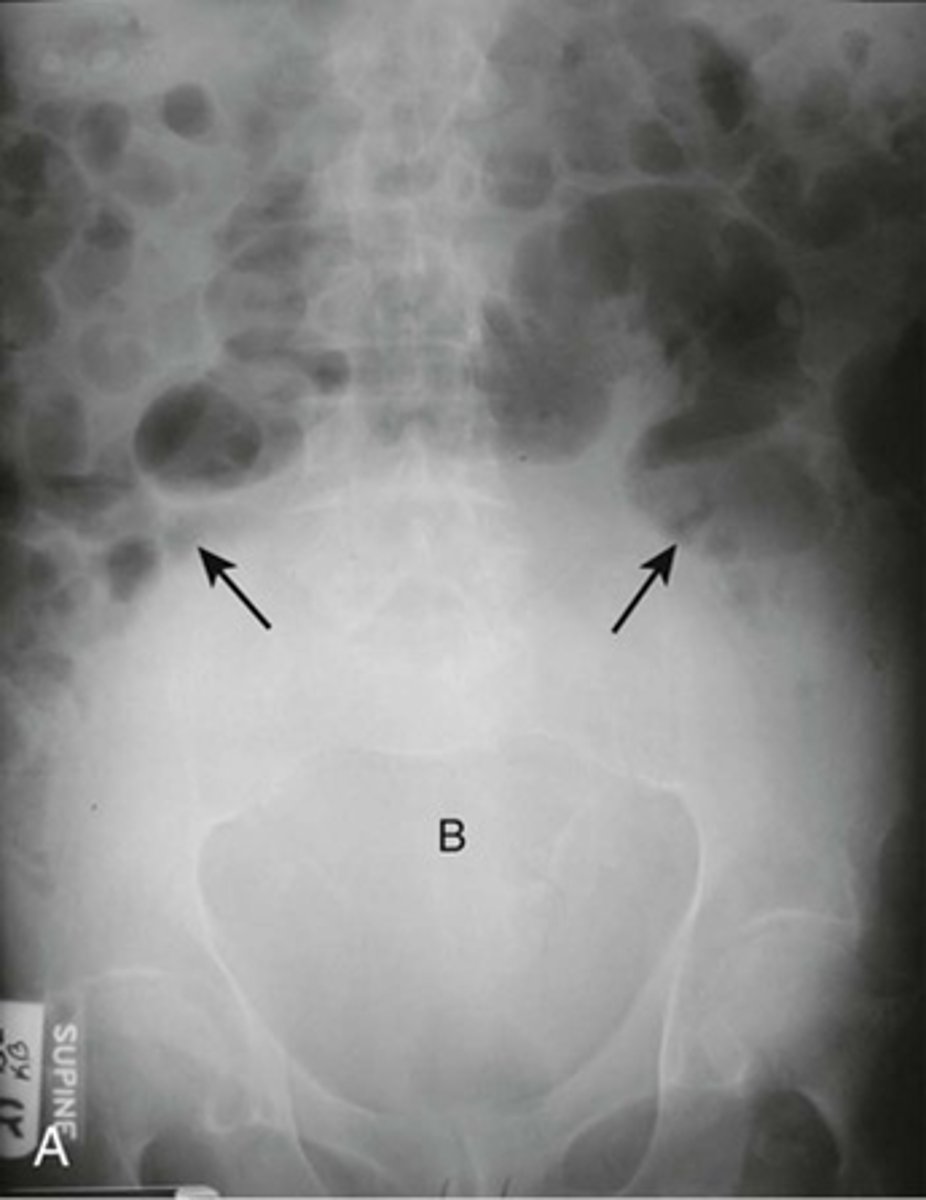

Distended bladder

Image A:

B: Distended bladder - soft tissue mass ascends from pelvis into lower abdomen, and displacing bowel.

BLACK ARROW: displacement of bowel into mid abdomen.

Image taken from 72y.o. male with bladder outlet obstruction due to BPH.